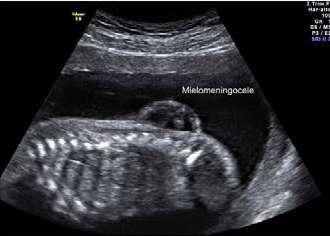

La forma más común y grave de espina bífida es el mielomeningocele (MMC), en la cual, una parte de la médula espinal y los nervios que la rodean atraviesan los huesos abiertos (vértebras) en la columna y salen a través de la espalda del feto. Por lo general, la médula espinal y los nervios expuestos están contenidos en un saco con líquido amniótico. Se cree que el contacto continuo de los frágiles nervios de la médula espinal

QUÉ ES LA ESPINA BÍFIDA? ES UNA MALFORMACIÓN CONGÉNITA EN LA CUAL UN ÁREA DE LA COLUMNA VERTEBRAL NO SE FORMA CORRECTAMENTE, DEJANDO EXPUESTA UNA SECCIÓN DE LA MÉDULA ESPINAL Y SUS NERVIOS A TRAVÉS DE UN DEFECTO EN LA ESPALDA. La espina bífida se estima que se presenta en 1,5 de cada 10,000 nacimientos vivos en Colombia y está anomalía congénita es más común del sistema nervioso central. En Colombia nacen entre 500 a 600 bebés con espina bífida cada año.

en desarrollo, con el líquido amniótico durante el transcurso de la gestación, y el impacto continuo de estos con la pared uterina, resulta en lesiones neurológicas progresivas e irreversibles. Hasta hace poco, el tratamiento de la espina bífida se limitaba a la reparación de defecto a las pocas horas del nacimiento, sin embargo, el daño sobre los nervios y la hidrocefalia ya estaban presentes.

Las características de la ecografía que sugieren una espina bífida incluyen una masa quística en cualquier lugar de la columna. Cuando se trata de un mielomeningocele se evidencia el defecto óseo sin la presencia del saco.

Bebé con Espina Bífida

Bebé con Espina Normal

Imagen ecográfica correspondiente a un mielomeningocele. Se evidencia la masa que contiene en su interior los nervios de la médula espinal.